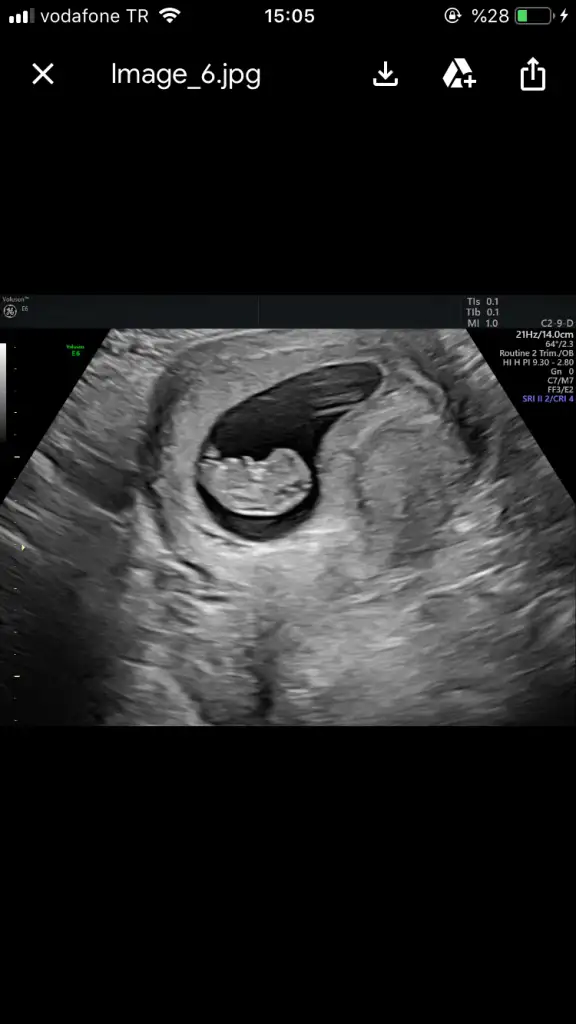

Ohoo daha 7+2de söyledi hemde baya erkek bu diye cok emindiSakin ol. Bende bi kayıp yasadıgım icin senin gibiydim. Acaba iyi mi kalbi atıyo mu bi sıkıntı var mı? Ama hic bi sıkıntı olmuyo. Kendi kendimizi yedigimizle kalıyoruz. Bebisin kıpır kıpır seni bekliyo olcakdoktor ne zaman dedi sana cok erken degil mi

Hoşgeldin canım bu düpedüz erkek yahuHoşbuldukkkayyy gerçekten mi inşaallah kızımın 12haftalık usg ile karşılaştırınca çok farklılar zaten 20gün geçmek bilirse öğreneceğiz inşaallah❤❤